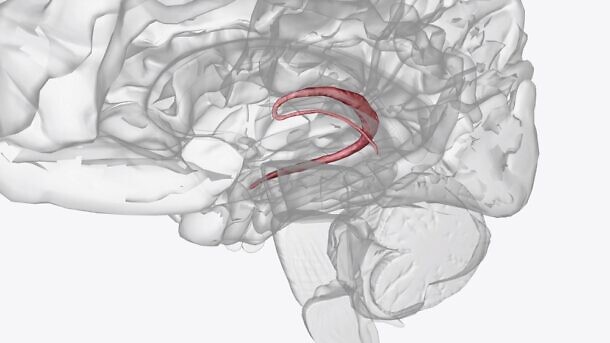

ישנה תחלואה ותמותה מרובה ממחלות בהם יש עליה בלחץ התוך-גולגולתי (Intracranial Pressure- ICP). תרופות רבות נמצאות בשימוש לצורך הפחתת ה-ICP, בהם אצטזולמיד וטופירמאט. עם זאת, הראיות שתומכות בשימוש בתרופות אלו אינן חד-משמעיות. במחקר זה החוקרים ביקשו לבחון את ההשפעה של אצטזולמיד וטופירמאט על הלחץ התוך-גולגולתי וההשפעה המולקולרית על מקלעת הדמים (Choroid Plexus- CP).

החוקרים השתילו חיישנים טלמטריים לזיהוי ICP במוחן של חולדות ממין נקבה על מנת להשיג מדידות ICP פיזיולוגיות במהלך תנועה חופשית של החולדות במהלך כל היממה. מחקר אקראי מוצלב בוצע בו חולדות קיבלו טיפול חד (על פני 24 שעות) עם מינונים גבוהים של אצטזולמיד וטופירמאט או טיפולים ממושכים (על פני 10 ימים) עם מינונים שווי ערך, כלל הטיפולים ניתנו דרך הפה. החוקרים ביצעו מערך לבחון ייצור והפרשה של נוזל מח-שדרה, RT-qPCR ותספיג חלבון בוצעו עבור CP in vivo ו-in vitro, על מנת לבחון את פעילות התרופות.